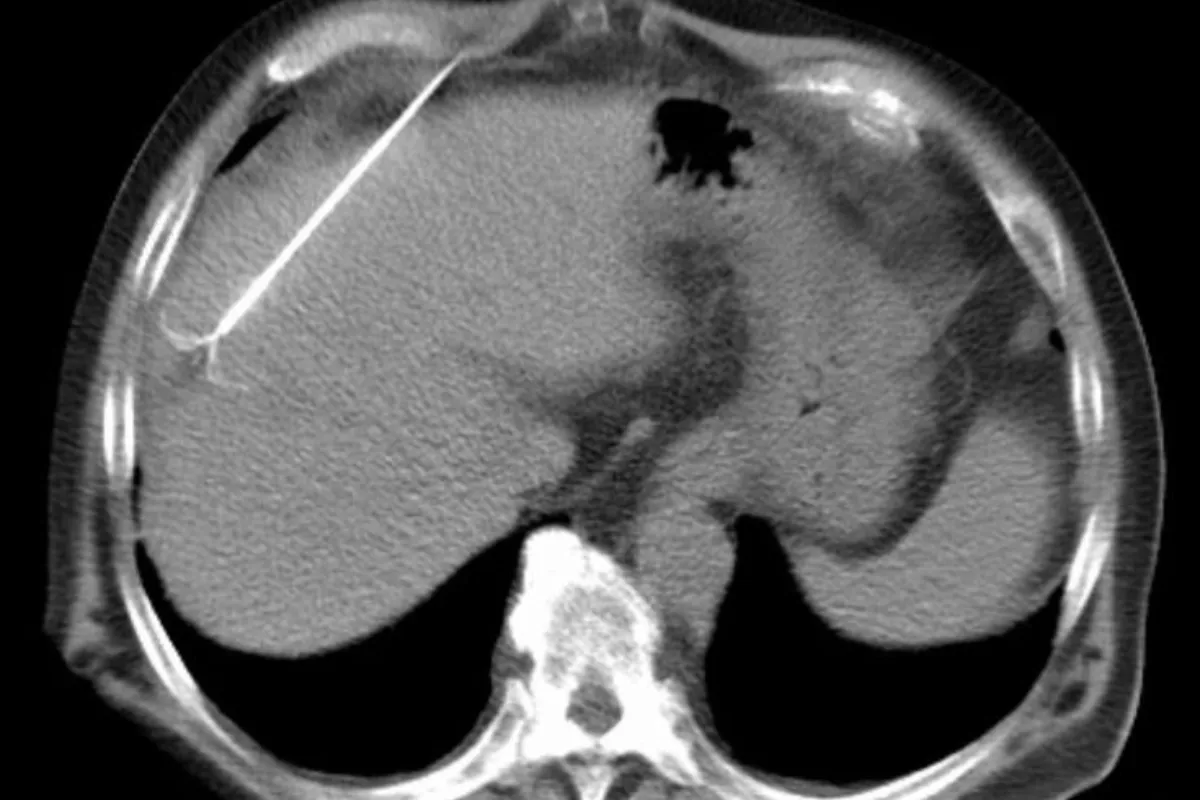

Interventional Radiology (IR) uses real-time imaging such as X-ray, ultrasound, CT, or MRI to guide tiny instruments through the body for treatment — without large surgical incisions.